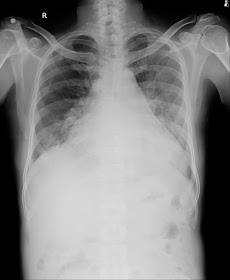

Respiratory system :

bilateral air entry- present

normal vesicular breath sounds heard

basal crepitations present in both the lung fields.